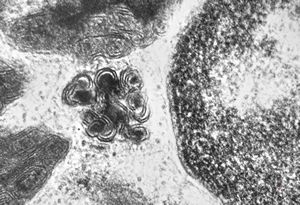

M,3y. | mast cell - granules with scroll-like formations - n. suralis, Krabbe globoid leukodystrophy

M,3y. | mast cell - granules with scroll-like formations - n. suralis, Krabbe globoid leukodystrophy

F,23y. | mast cell - granules with scroll-like formations - n. suralis, demyelinating neuropathy

F,31y. | mast cell - granules with scroll-like formations - n. suralis, demyelinating neuropathy

M,12y. | mast cell - granules with scroll-like formations - skin, urticaria pigmentosa